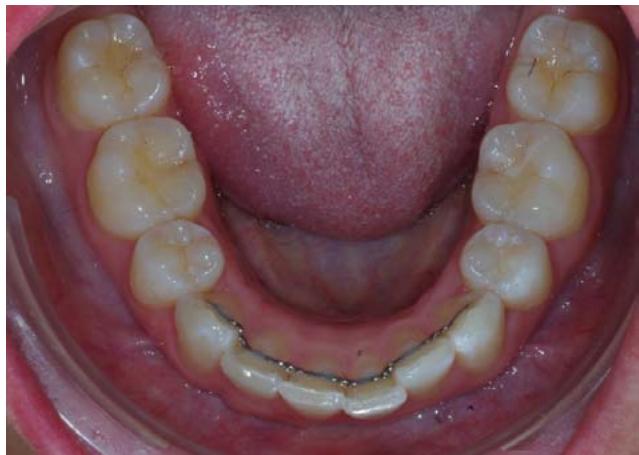

L'examen endobuccal montre une supraclusion incisive, une DDM et un sens transversal correct. Dans le sens sagittal, on note une classe Il dentaire.

Examen endobuccal